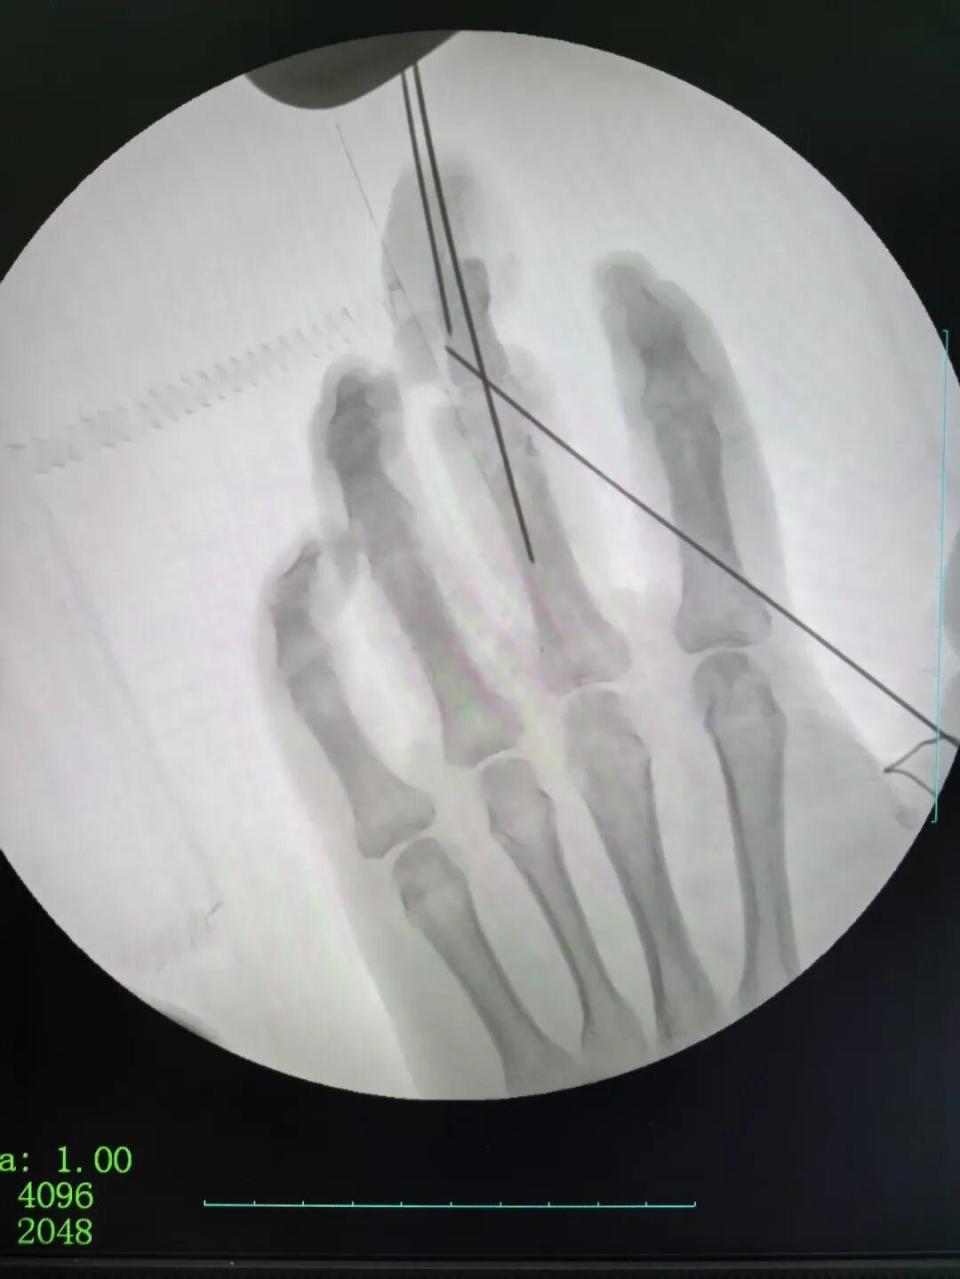

2026年1月1日,手足显微修复重建专家刘金海及其团队已坚守在手术台前,成功为一位远道而来的手指缺损患者完成显微修复重建手术,以医者的责任与担当开启新岁。刘金海在开年寄语中如是写道:

2026年的第一天,新年的钟声还在耳畔回响,我和我的团队却已在手术室为一位远道而来的手指缺损患者完成了显微修复重建手术。以一台手术开启新岁,于我而言,既是医者的日常,更是对“健康所系,性命相托”誓言的践行。